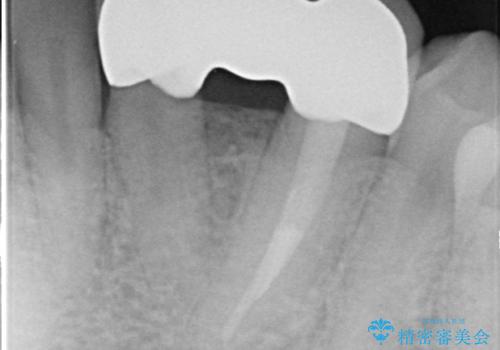

左下123番のブリッジになるが、左下1番と3番の歯軸が合っておらず神経治療が必要になる可能性があるため部分矯正を提案したところ、希望されなかったため、そのままの歯軸でオールセラミッククラウンによる補綴を行いました。

- オールセラミッククラウン…¥100,000×3、仮歯…¥10,000×3、ファイバーコア…¥20,000費用は治療当時の料金となります

- 根管治療により痛みや腫れがひかない事や、術後に痛みや腫れが生じる事、治療によるファイル破折やパーフォレーションなどの偶発症、術後の歯根破折を生じる可能性もあります